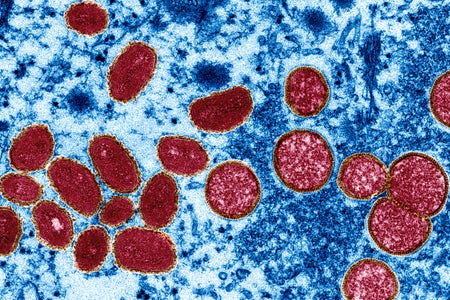

Why is Monkeypox Evolving So Fast?

The virus circulating in the current outbreak has mutated 50 times in the past four years